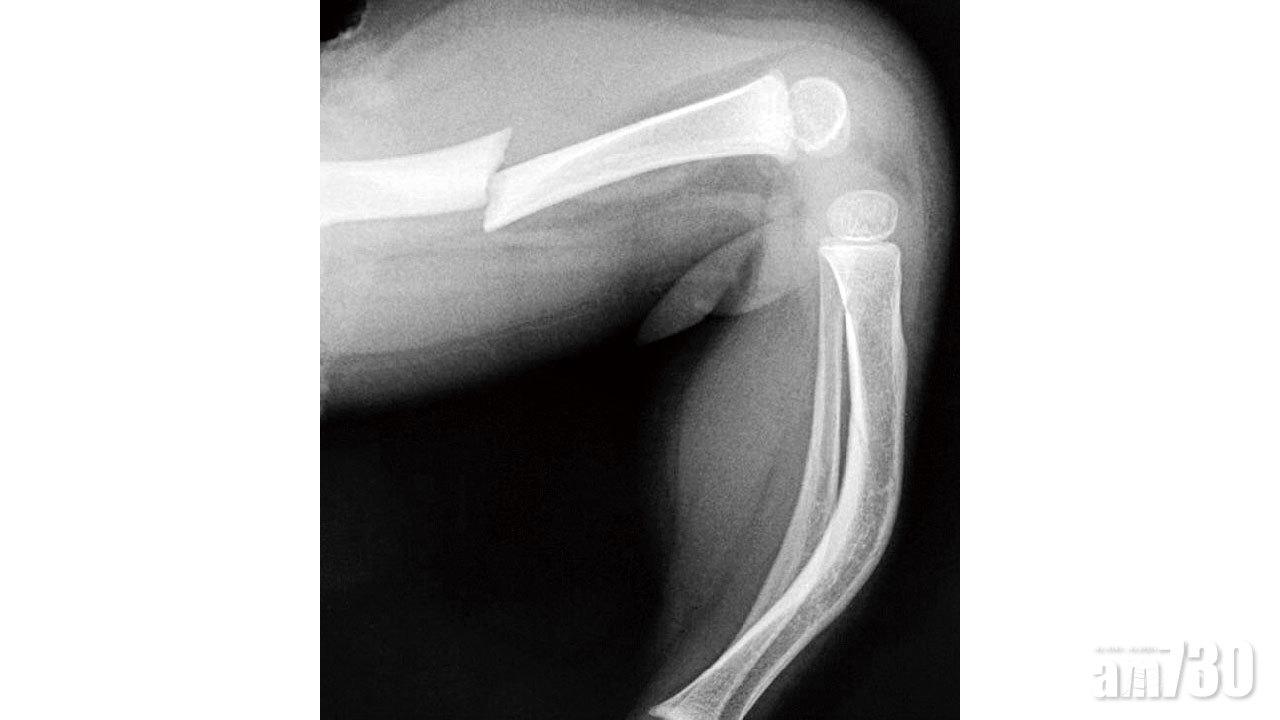

患上玻璃骨的「瓷娃娃」,早於學行前便開始因輕微碰撞,或在毫無創傷記錄下,在四肢各處重複地骨折,需經常入院治療。其骨折的治療方案,大致上都與一般小兒骨折無異,包括照X光檢查,就嚴重程度選擇打石膏、戴矯形器或做內固定手術。雖然此症不會影響骨折自然愈合,但因失去重塑能力,四肢骨骼會逐漸變形。至於脊椎也會形成脊柱側彎與後凸,最終患者個子也較為矮小。

隨着長大後骨骼成形,患者骨折的次數也會明顯減少。但要在童年時扭轉經常骨折的厄運,醫生或會處方用於治療骨質疏鬆的雙磷酸鹽,並在四肢骨折或做矯形手術時,使用可延長的髓內釘來固定,一來可強化骨骼的承重能力,二來能減少日後需重做手術的次數。作為照顧者的家長,既要對瓷娃娃呵護備至,又時刻生怕意外骨折,如何拿捏輕重方寸,委實不易。